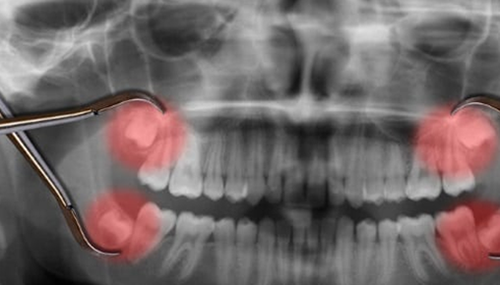

9、智齿

这几乎是每个人都不得不接受的痛苦经历,但你有没有想过它们为什么会存在?答案是饮食。在过去,我们的饮食包括各种各样的东西,比如树叶、生肉和树枝,所以我们的下巴比现在大得多。智齿帮助我们管理我们多样化的饮食,更大的下巴为额外的牙齿留出了空间。尽管如此,多年来,下巴仍在收缩以适应更多的需求。